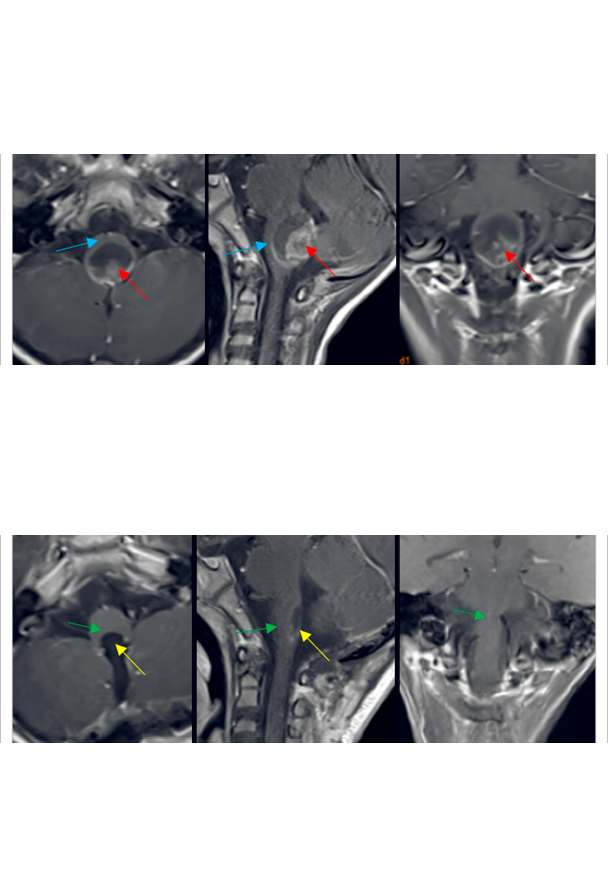

“肿瘤位置太不同、手术困难太大,残疾的可能性很大……”一位22岁髓内肿瘤占位的男士,颈后部疼痛,手臂麻木半年。咨询了国内一些大医院,医生们都这样告诉他。好在咨询了很多国外治疗办法,得知INC国际神经外科顾问团有位被国内尊称为“巴教授”对脊髓髓内、脑干等“手术禁区”内的肿瘤切除较为擅长。于是通过INC前往教授所在医院德国INI接受治疗,教授对其行髓内占位切除术、颈5-6椎体成行术,瘤体强化部分被完整切除。术后10天出院,精神状态佳。

胶质瘤是起源于神经胶质细胞的肿瘤,可以发生于大脑及脊髓的任何部位,而侵犯颅内脑干同时延伸累及颈髓甚至胸髓,这样病变范围广的胶...